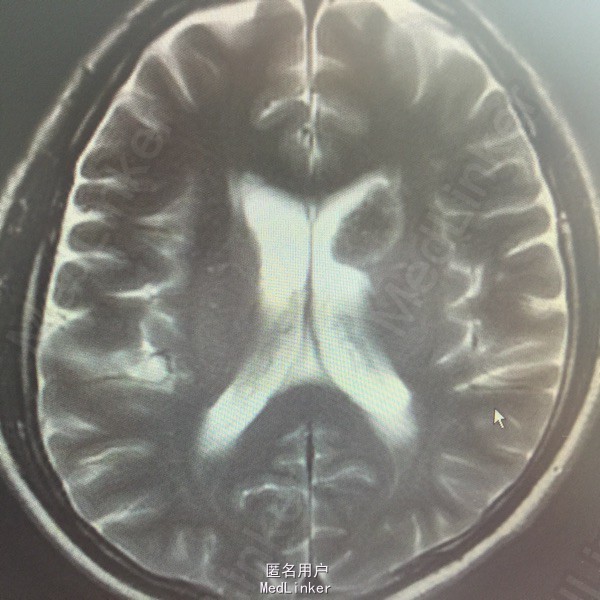

男,54岁,以头痛半个月入院。 现病史:半个月前无诱因头痛,呈胀痛,无呕吐,无意识障碍,病来咳嗽、咳痰,体重减轻约5斤,无发热。 既往史:无特殊。

查体:BP:150/100mmHg,神清语明,两瞳孔等大正圆,直径约3.0mm,光敏,四肢肌力5级,肌张力正常,腱反射艹,左侧共济运动阳性,病理征阳性,脑膜刺激征(-)。 辅查:见下:

肺癌脑转移。 影像解读(影像如何解读是临床工作中非常重要的一环)。 左侧额叶近皮质长Tl长T2信号,局部颅骨缺损,右侧枕叶不规则病灶,TlWl呈中心呈等信号,周围高信号,T2Wl呈高低混杂信号,伴大片水肿,相邻侧脑室后角、胼胝体受压。增强呈不规则环环强化。 已进行局部放疗治疗。